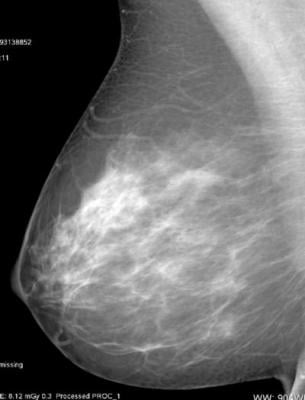

July 2, 2018 — A large Norwegian study using automated breast density measurements found that women with mammographically dense breast tissue have higher recall and biopsy rates, and increased odds of screen-detected and interval breast cancer. The study, published online in the journal Radiology, supports automated measurements as a future standard to ensure objective breast density classification for breast cancer screening, the researchers said.

Previous studies have shown that women with mammographically dense breasts face a higher risk of breast cancer and missed cancers than those with non-dense breasts, partly because the superimposition of dense breast tissue on mammograms leads to a masking effect, causing some cancers to go undetected. However, the majority of those studies relied on subjective density assessments — most commonly, the radiologist’s subjective interpretation using the American College of Radiology’s Breast Imaging Reporting and Data System (BI-RADS). This approach introduces potential mammogram reader variability into density categorization, said the study’s principal investigator, Solveig Hofvind, Ph.D., from the Cancer Registry of Norway in Oslo.

For the new study, Hofvind and colleagues used automated software to help classify mammographic density in 107,949 women ages 50 to 69 from BreastScreen Norway, a national program that offers women screening every two years. The researchers looked at a total of 307,015 digital screening examinations that took place from 2007 to 2015.

The automated software classified breasts as dense in 28 percent of the screening examinations. Rates of screen-detected cancer were 6.7 per 1,000 examinations for women with dense breast tissue and 5.5 for women with non-dense breasts. Interval breast cancer, or breast cancer detected between screenings — usually by palpation — was 2.8 per 1,000 in the dense breast tissue group and 1.2 for women with non-dense tissue.

The recall rate, or rate at which women are called back for additional examination based on suspicious mammographic findings, was 3.6 percent for women with dense breasts, compared with 2.7 percent in women with non-dense breasts. The biopsy rate of 1.4 percent in the dense breasts group was higher than the 1.1 percent rate for women in the non-dense category.

Mammographic sensitivity for detecting breast cancer was only 71 percent for women with dense breasts, compared to 82 percent for women with non-dense breasts. Cancers detected at screening were more advanced among women in the dense breast tissue group. Average tumor diameter for screen-detected cancers was 16.6 millimeters (mm) in the dense breasts group, compared to 15.1 mm for the non-dense group. Lymph-node-positive disease was found in 24 percent of women with dense breasts, compared with 18 percent for women with non-dense breasts.